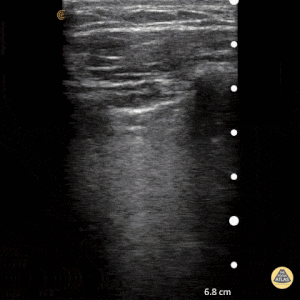

2

Based on the ultrasound image above, which shock etiology is most likely?

1 pts